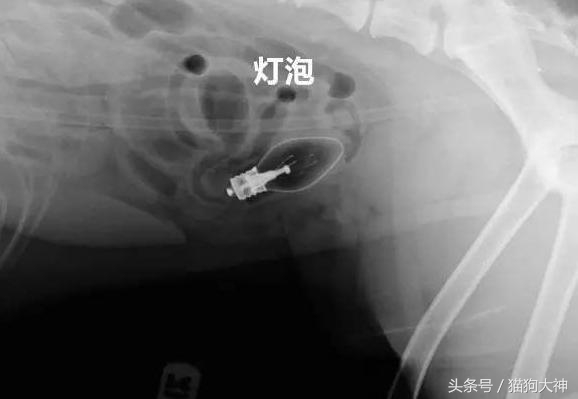

这只吉娃娃竟然吞下了九根针,主人发现时,针已经在全身上下游走,情况非常危险。